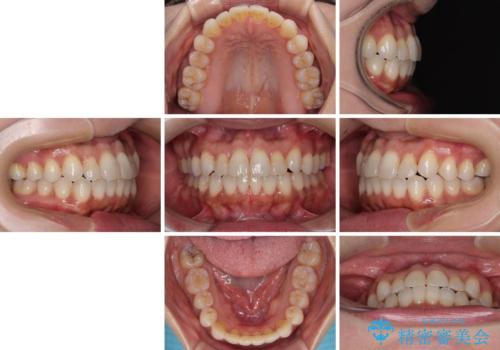

前歯のクロスバイト インビザラインによる矯正治療

- 上下のクロスバイトと前歯のデコボコを気にして来院された患者様です。

インビザラインを用い、IPR(歯と歯の間を削る)と歯列全体を拡大させることで、歯並びを整えていくこととしました。

インビザライン特有の、治療後半に奥歯が咬み合わないという事象が長引きました。

咬み合わないときの対処方法は色々とありますが、ゴムかけなどを活用して噛めるようにしました。